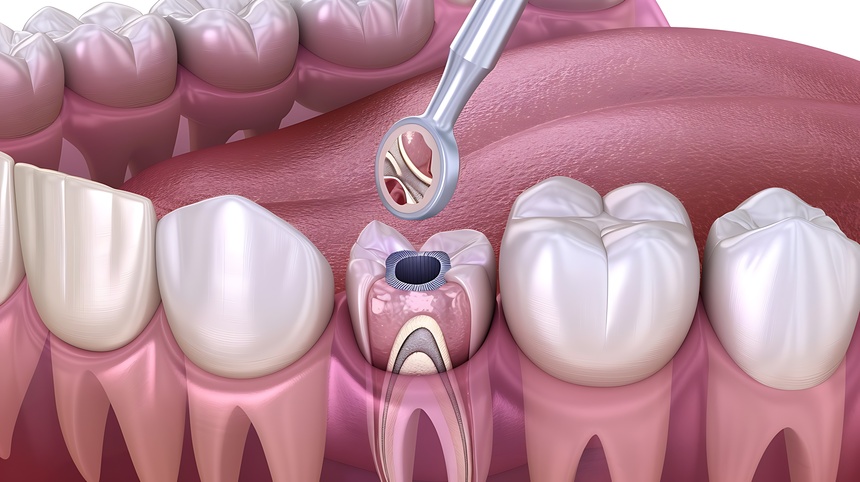

Painless Root Canal Treatment in Nashik | Care32 Dental Centre

Root canal treatment is often feared due to misconceptions about pain and discomfort. At Care32 D...

Painless Root Canal Treatment near College Road Nashik | Care 32

Discover the benefits of Painless Root Canal Treatment in College Road Nashik at Care 32 D...